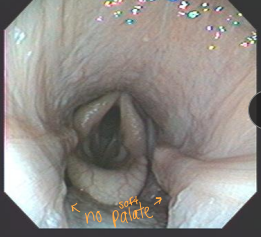

Cleft palate: milk in nostrils from birth; aspiration pneumonia; Dt w/ endoscopy; Tx w/ Sx

4th branchial arch defect: rare; resp noise, poor performance, cough, aspiration; Dt: “rostral displacement of palatopharyngeal arch”; No Tx